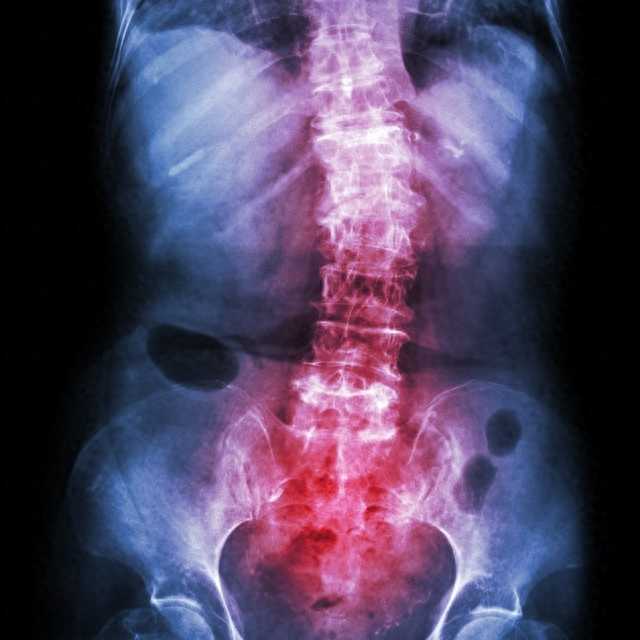

曾几何时,中国的歌坛巨星李宇春,因脊柱健康问题一度坐轮椅,引起了广泛的关注。

强直性脊柱炎是一种自身免疫性疾病,它也被戏称为“不死的癌症”,因为它无法被完全根治且易于复发。

强直性脊柱炎的症状在初期可能并不明显,通常表现为腰背疼痛。

然而,如果不及时治疗,疾病会逐渐恶化,导致脊椎骨融合。

这会影响到基本的日常动作,如低头、弯腰和转身。此外,误诊率相对较高,因为早期症状可能与其他疾病相似。